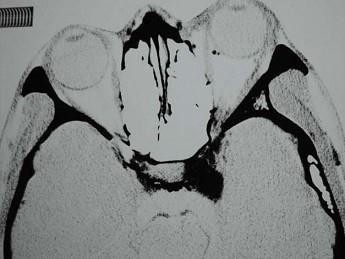

问题 男,44岁,车祸伤及右侧眉弓和头部,当时右眼上、下睑青紫淤血,半月后右眼球结膜高度水肿视力下降,右眼球突出,CT检查如图,最可能的诊断为()

选项 A.眶内静脉曲张 B.颈内动脉海绵窦段动脉瘤 C.海绵窦动静脉瘘 D.脑动静脉畸形 E.硬脑膜动静脉瘘

答案 C